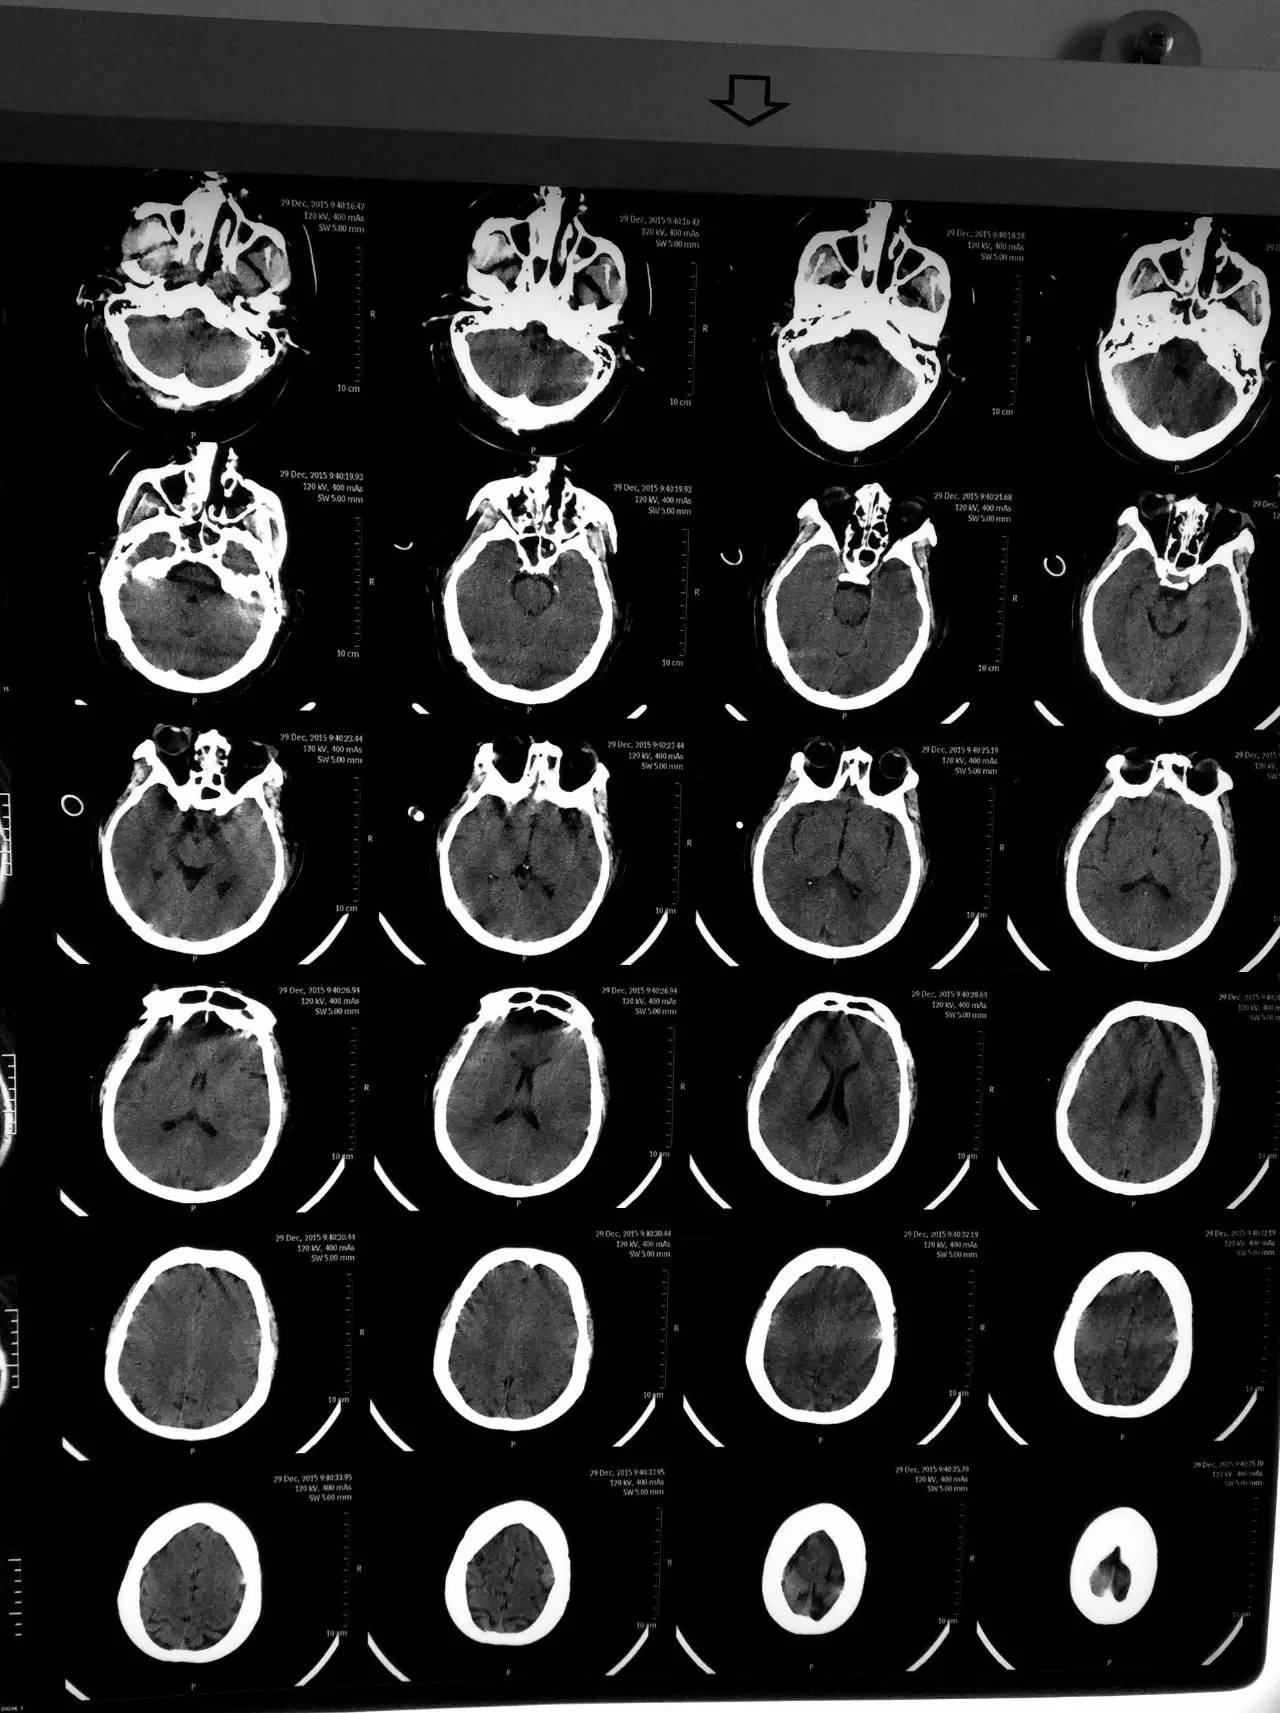

▼患者影像资料